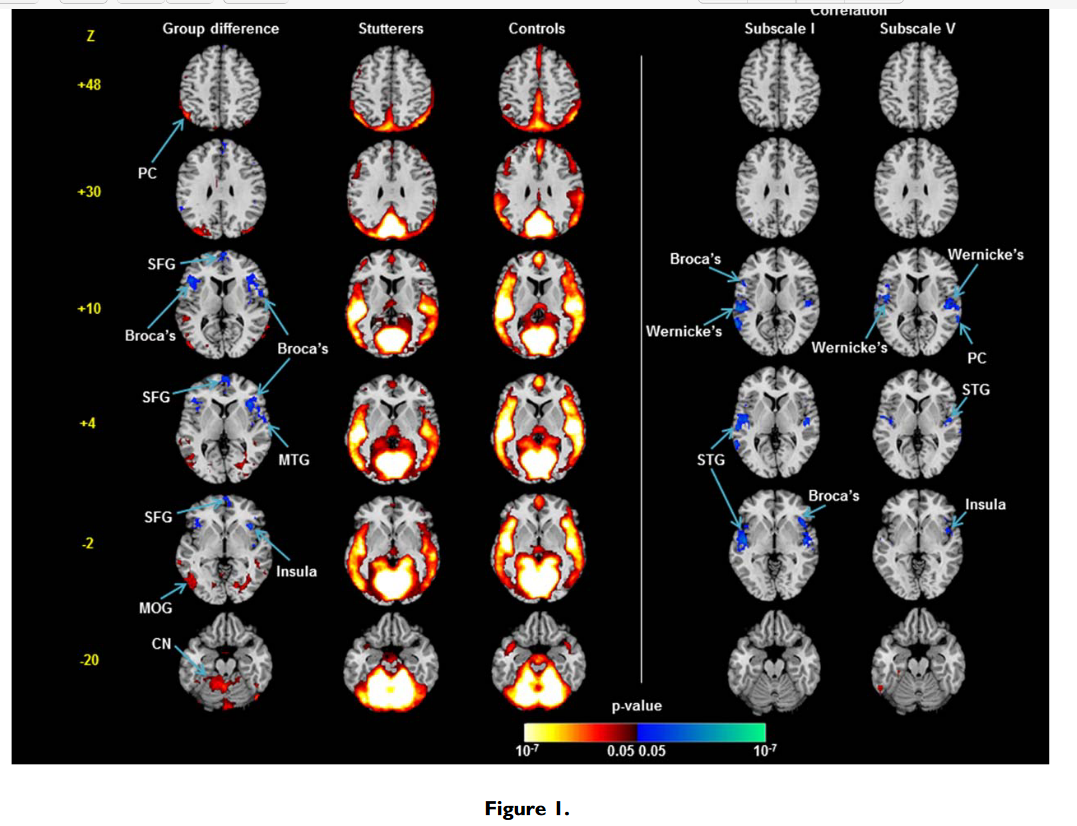

样本特征:与口吃者相比,对照组的智商全面得分略高,具有统计学意义。 组间灌注值对比:与流利的对照组相比,口吃组的Broca区 (P < 0.0043) 和额上回 (P < 0.0015) 的静息 rCBF 值较低 (P < 0.0001)(图 2)。

这项研究首次使用灌注MRI来研究口吃者的大脑活动差异。与健康对照组相比,口吃组静息状态下双侧Broca区和额上回rCBF降低,Broca区rCBF值与口吃严重程度呈负相关,并向后延伸至语言环路的其他部分;与健康对照组相比,口吃组小脑核团和顶叶皮层的rCBF增加。在儿童分析中,所有发现都没有改变。不同年龄阶段研究结果的一致性表明,Broca区rCBF降低可能代表了一种稳定的特质脆弱性,没有这种脆弱性,口吃可能不会表现出来。灌注与口吃严重程度的负相关表明,口吃越严重,Broca区和语言环路后部的rCBF降低越大。 Broca区是用于语音生成的神经网络的关键组成部分,Broca区局部脑血流量的降低会干扰运动规划、语音和句法加工以及词汇提取,导致非流利性。这种严重程度的相关性向后延伸至弓状束的邻近组织,提示当Broca区存在的组织紊乱向后延伸至弓状束时,语言环路功能恶化,产生更严重的症状。对所有参与者的rCBF与运动表现的相关性进行的事后分析支持了对主要发现的解释。使用优势手的手指敲击速度与对侧感觉和运动语言区rCBF的正相关表明,更好的运动表现伴随着语言区更大的rCBF,口吃者语言区rCBF的减少不仅代表言语行为的计划和执行,而且更普遍地代表简单的感觉运动过程。rCBF 与语言区头侧双侧感觉运动区优势手的手指敲击速度呈负相关,这表明在感觉运动皮层中需要相对较少 rCBF 以产生相当水平的运动表现的人,这种简单运动任务的速度更快因此,它们的感觉运动皮层中的神经处理效率更高。 额斜束是连接布罗卡区和额上回的深层额叶通路,额上回负责语言的启动和自发性。该束的损伤会导致言语减慢和停顿。额上回区域 rCBF 减少可能反映斜束中的组织紊乱。神经影像学和病变研究表明,小脑核团有助于言语运动控制。在口吃组中,小脑 rCBF 的增加可能代表对Broca区和相关语言回路中存在的基于运动的不流畅的补偿反应。同样,顶叶皮层 rCBF 的增加可能代表使用高阶、多感觉整合过程来补偿口吃组的不流畅,因为功能性 MRI 研究表明顶叶皮层与参与言语产生的初级感觉运动区域有广泛的联系。感觉运动语言系统以外区域的异常 rCBF 表明网络的参与超出了负责正常语音产生的关键解剖区域。